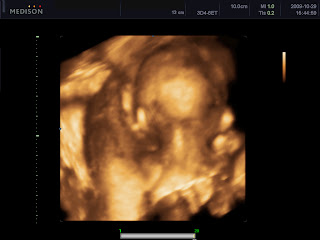

Íme egy fotó, Kedves beleművészkedett, hogy egyértelműbb legyen. Engem egy kedves indiai nőce vizsgált, ő volt a tanító, és ketten vizsgálódtak még. Sokáig nézte a szívét, azt mondta, hogy olyan szülészorvost keressek, aki tudja követni a baba szívét, mert valami olyat észlelt, hogy aszinkronocitás van, nem nagy baj, csak valami nem pont egyszerre működik.....nem egyszerre húzódik össze, vagy valami ilyesmi... Kép

Kép